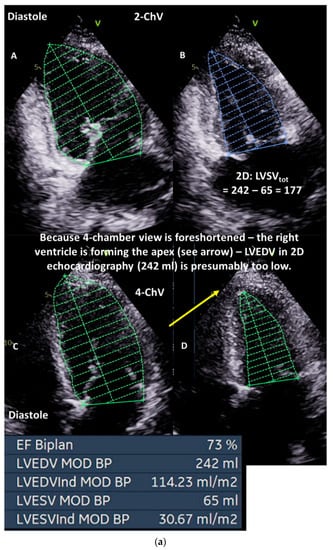

Figure 3.

(a): Illustration of underestimation of LVEDV and LVESV by 2D echocardiography: in (A), the planimetry of LVEDV in the two-chamber view (2-ChV) is shown; in (B), the corresponding LVESV is shown. In (C), the planimetry of LVEDV in the four-chamber view (4-ChV) is shown; in (D), the corresponding LVESV is shown. However, the obvious difference between the longitudinal LV axis in the 4-ChV between diastole and systole indicates the foreshortening of the 4-ChV causing errors of LV volume assessment. LVSV = left ventricular stroke volume, LVSVtot = total LVSV, LVSVeff = effective LVSV, LVEDV = left ventricular end diastolic volume, and LVESV = left ventricular end systolic volume. (b): Measurements of the corresponding LVEDV areas in adjusted sectional planes by postprocessing in a 3D dataset in comparison with the 2D echocardiography presented in (a): in (A), the LVEDV assessment of the adjusted four-chamber view is shown; in (B), the perpendicular lines of the apical planes in the short-axis view of the 3D dataset are shown; in (C), the 3D view of the azimuth plane is shown; in (D), the LVEDV assessment of the adjusted two-chamber view is shown. In (E), a parasternal short-axis view during systole to label the RVOT is shown. In (F), the RVOT-pw-Doppler spectrum is shown. In (G), a parasternal long-axis view during systole to label the LVOT is shown. In (H), the LVOT-pw-Doppler spectrum is shown. Estimation of effective LVSV is performed with pw Doppler echocardiography by determination of forward RVSV. In isolated mitral regurgitation, a countercheck can be performed by assessment of forward LVSV which corresponds to forward RVSV. LVSV = left ventricular stroke volume, RVSV = right ventricular stroke volume, LVSVtot = total LVSV, LVSVeff = effective LVSV, LVEDV = left ventricular end-diastolic volume, RVOT = right ventricular outflow tract, and LVOT = left ventricular outflow tract.